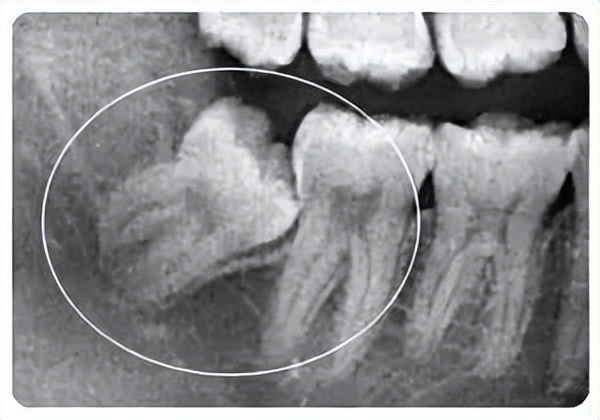

1.埋伏牙一直隐藏在颌骨中如果不及时处理,可能对离得近的健康牙齿造成损伤,形成囊肿。

2.埋伏牙还会影响整排牙齿的排列,挤歪其他的牙齿会造成咬合紊乱异常。

直接拔除的情况一般是针对长得歪斜奇怪,有可能会影响正常牙齿健康的才会考虑拔除,如埋伏智齿,影响邻牙健康的话一般都会建议拔除。